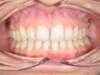

Encombrement aux deux arcades.Traitement par gouttières.

Avant

Après